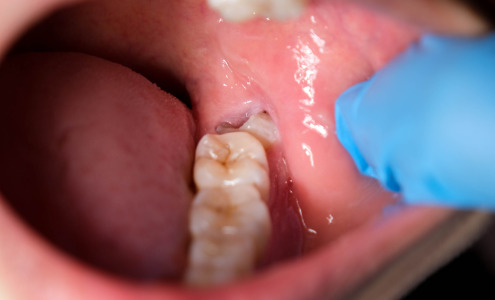

Wisdom teeth often erupt in late teens or early adulthood and can sometimes lead to pain, crowding, or gum infections. At Dolphin Dental Hospital, we specialize in painless tooth extraction, ensuring a smooth, stress-free experience.

Impacted wisdom teeth are causing pain

Our doctors use advanced anesthesia and minimally invasive techniques to provide painless tooth extraction. With skilled hands and gentle care, we make sure your treatment is comfortable from start to finish.